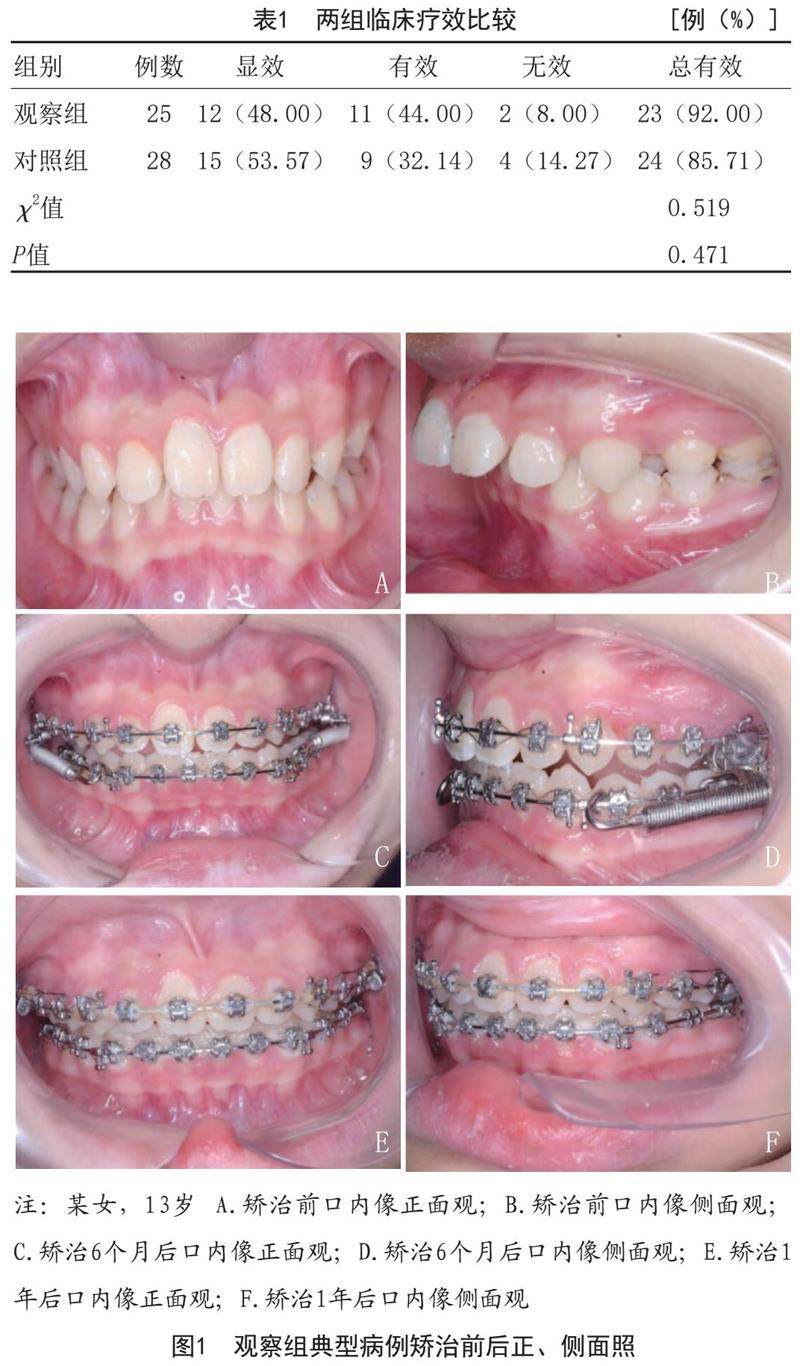

[摘要]目的:探讨Forsus矫治器治疗下颌后缩型安氏Ⅱ类患者对颞下颌关节影响的CBCT分析研究。方法:选取2018年2月-2021年2月笔者医院收治的53例下颌后缩型安氏Ⅱ类患者为研究对象,采用随机数字表法分为观察组(n=25)和对照组(n=28),观察组采用Forsus功能矫治器进行矫治,对照组采用Twin-block功能矫治器进行矫治,两组均佩戴1年后,对比两组治疗效果,对比治疗前后上下齿槽角指标、骨性指标及上下颌中切牙指标。(剩余9907字)